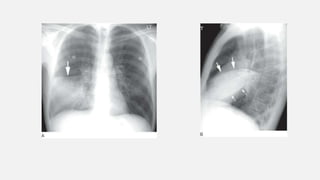

• #45 he silhouette sign in right middle lobe pneumonia. A: Consolidation of the right middle lobe obscures (“silhouettes”) the right heart border (i.e., it is not clearly seen).In contrast, the left heart border is sharply marginated. The right hemidiaphragm appears sharply marginated. The pneumonia is marginated by the minor fissure (arrow). B: On the lateral view, middle lobe consolidation is visible, marginated above by the minor fissure (large arrows); inferiorly, it is marginated by the major fissure (small arrows).

• #46  The silhouette sign in right lower lobe pneumonia. A: The frontal view shows right lower lobe consolidation with obscuration of the diaphragm. The right heart border (arrows) remains visible as an edge. B: On the lateral view, complete right lower lobe consolidation is visible, outlined anteriorly by the major fissure (white arrows). The right hemidiaphragm (large black arrows) is sharply marginated anterior to the consolidated lobe but is invisible posteriorly. The posterior left heart border and left hemidiaphragm are sharply marginated (small black arrows).